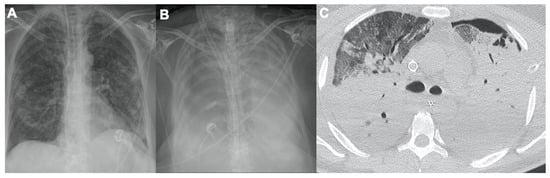

2.2. Acute Respiratory Disease Syndrome

2.3. Pulmonary Embolism